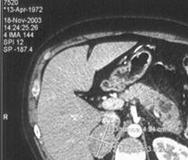

Другим примером является прямая радионуклидная

цистография. Методика исследования включает катетеризацию уретры, ретроградное

заполнение мочевого пузыря физиологическим раствором хлорида натрия, смешанного

с меткой, и получение с помощью гамма-камеры изображений области мочевых путей

во время заполнения пузыря, в момент мочеиспускания и после него. Полученное

изображение приведено на Рис. 3.

Рисунок 3 - Радионуклидная диагностика мочевого

пузыря.